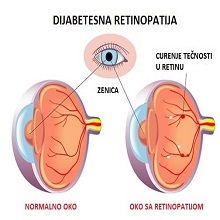

Диабетес меллитус је веома чест метаболички поремећај, у коме продужена хипергликемија настаје као последица недостатка и/или умањене ефикасности ендогеног инсулина. Диабетес може да буде инсулин зависни ( ИДДМ) и инсулин независни ( НИДДМ), односно тип 1 и тип 2. |